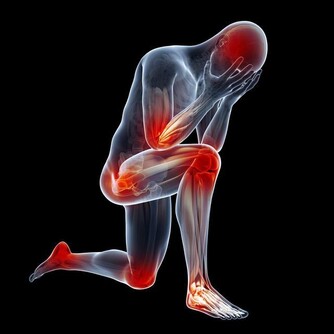

大部分肝癌患者到了晚期都會有很明顯的疼痛感,而早期很少有疼痛情況出現,一般出現明顯的疼痛都已發展到中晚期了,但是有疼痛并不代表就是肝癌,需要分清楚是哪裡疼痛,然後再進行針對性的檢查。

*****6.轉移灶的疼痛*****

肝癌會轉移到其他部位,比如轉移到肺部、骨骼處、那麼就可能出現骨痛、胸痛的情況。

如果有肝癌與多部位的疼痛都有一定的關係,除了關注疼痛之外,還要及時了解肝癌的症狀以及相關檢查。